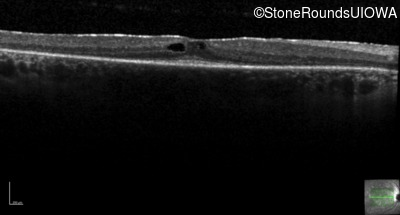

Optical Coherence Tomography - Left -

20/20

Exemplar / OCT Stack